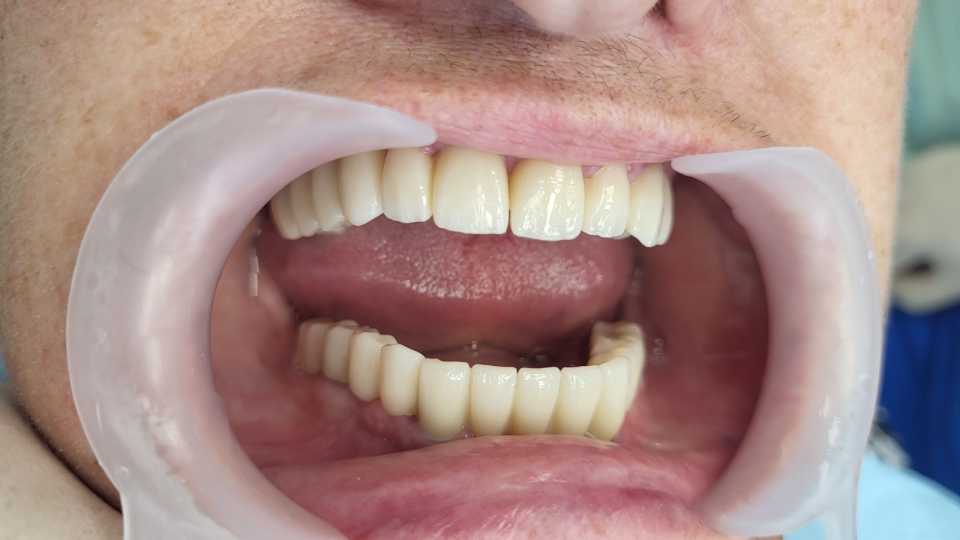

Planul de tratament a inclus extracția dinților parodontotici la nivelul mandibulei și inserarea a 5 implanturi dentare Mega-Gen AnyRidge cu conexiune multiunit, urmată de protezarea acestora cu o lucrare fixă, înșurubabilă, din ceramică pe suport de zirconiu.

La nivelul maxilarului, s-au efectuat extracțiile dinților parodontotici, tratamentul laser și chirurgical al leziunilor parodontale, urmate de reabilitarea protetică prin realizarea a două lucrări fixe din ceramică pe suport de zirconiu.